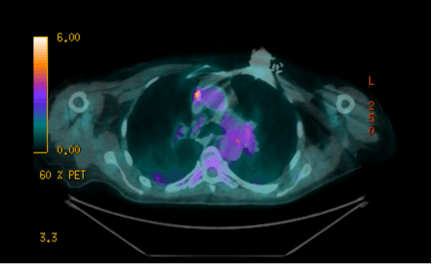

Poster abstracts – FPM Centenary Conference – 7th December 2018

16 1b